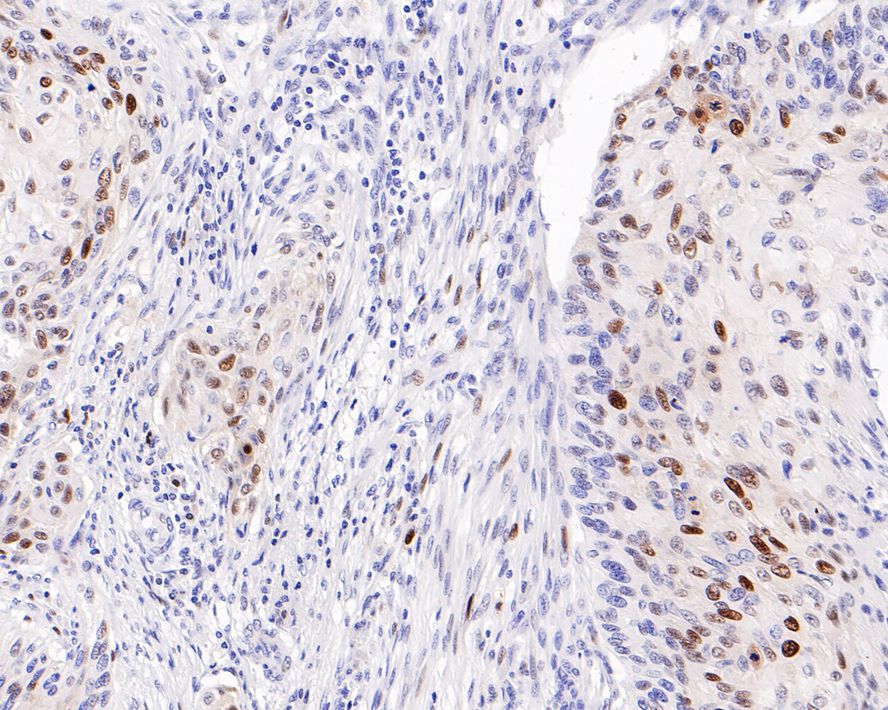

Catalog# HA601017

p21 Mouse Monoclonal Antibody [A8C12]

IHC-P

Human